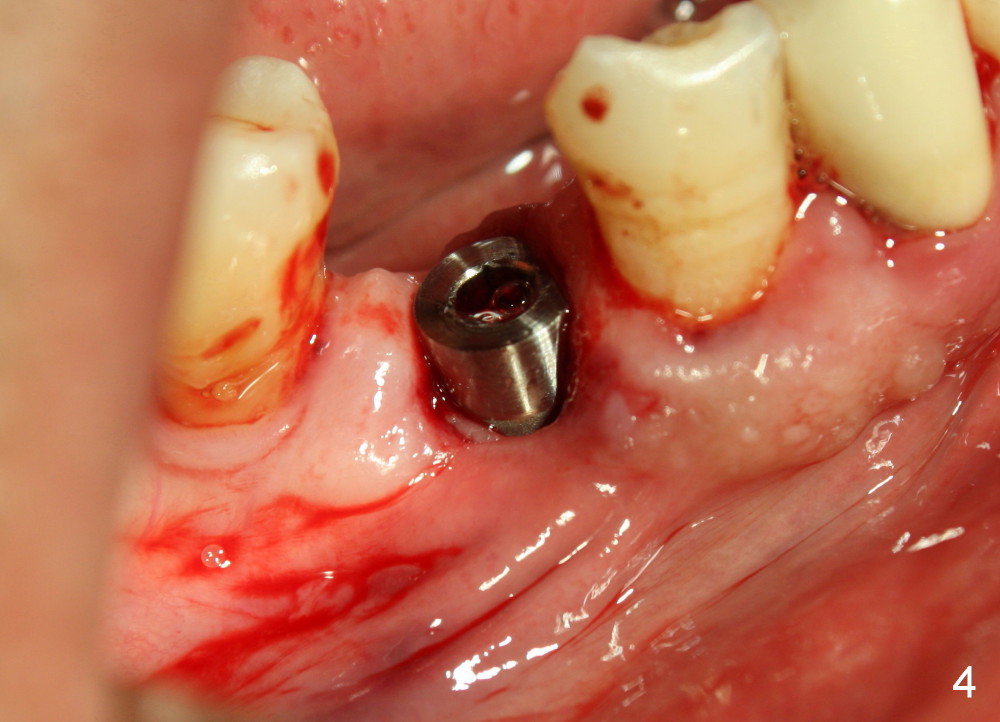

A 66-year-old man has poor dentition (Fig.1). Several teeth (x) including #28 need extraction and implants. The tooth #28 is extracted (Fig.2), followed by immediate implant (5x17 mm, Fig.3 I). There is more buccal gingival recession over the implant (Fig.4), which is less prominent 1.5 months postop (Fig.5). The definitive restoration is delivered less than 2 months postop (Fig.6), because of travel abroad. The patient agrees not to chew with the Emax crown. Five months later, he returns with chipped porcelain (Fig.7 arrowhead). It appears that immediate implant can survive early and over loading. More implants are necessary to share the masticatory loading. Since there is malocclusion, where to place implants appears to be critical (Model 3 30 4 5 6 7). There is no bone loss 4.5 years (Fig.8) or 5 years 8 months (Fig.9) post cementation.